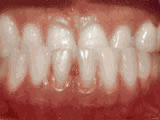

Missing lateral incisors

This patient's lateral incisors were congenitally missing. She had braces for 20 months to move the teeth into their correct positions, then the missing teeth were replaced with bonded "Maryland" bridges.